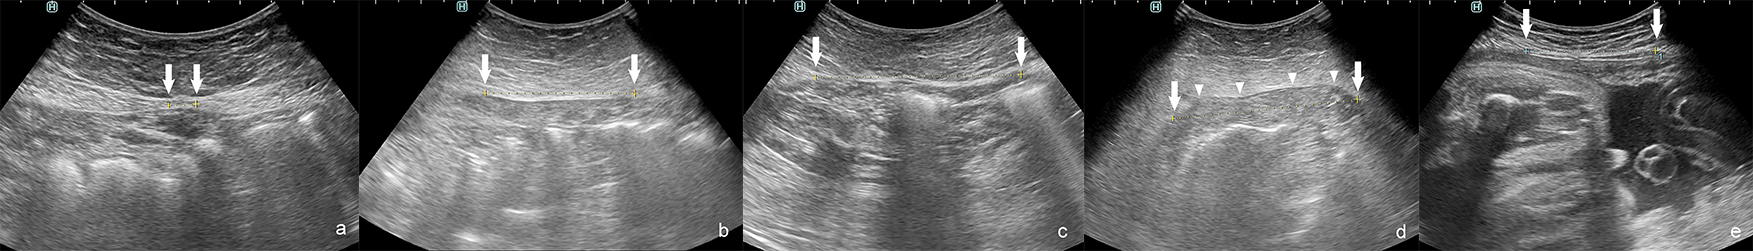

To diagnose the presence of DRA and its severity the interrecti distance (IRD) is measured [4]. Palpation, caliper, ultrasound (Fig. 3), CT (Fig. 4) and MR are used to measure IRD [2, 4]. To date there is no consensus which method should be applied. Swedish national guidelines recommend diagnosis using caliper or ruler for measurement. Ultrasound or other imaging modality is recommended when concomitant hernia is suspected [7]. Corvino et al. [17] promote the use of dynamic ultrasound in case of suspected hernia. They point that computed tomography is a static examination, while dynamic ultrasound could demonstrate the movement of abdominal contents [17]. The finger-width method is widely used, as it is economical and relatively convenient [2]. However, ultrasound, CT or MR to measure IRD are more accurate and may exclude any concurrent ventral hernia [2, 6].

Fig. 3.Interrecti distance (IRD) measured by ultrasonography: correct IRD 8 mm. (a) Examples of diastasis recti abdominis (DRA). (b–e) IRD 66 mm. (b) IRD 74 mm. (c) IRD 82 mm during curl up. (d) IRD 52 mm in pregnant woman. (e) Arrows–medial margins of rectus muscles, arrowheads–protruded linea alba during curl up.